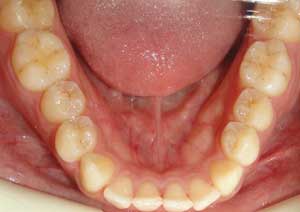

Traitement : Dans ce cas, nous avons eu recours à la mise en place de cales postérieures en résine bleue au niveau des premières molaires maxillaires, Elles ont permis de séparer temporairement les mâchoires afin de laisser les dents du haut se replacer correctement devant celles du bas, corrigeant ainsi le cross-bite antérieur.

Par la suite, ces cales ont été déplacées sur les faces palatines des incisives maxillaires dans le but d’optimiser l’articulé postérieur, notamment au niveau des molaires droites, qui présentaient également un articulé inversé.

Après